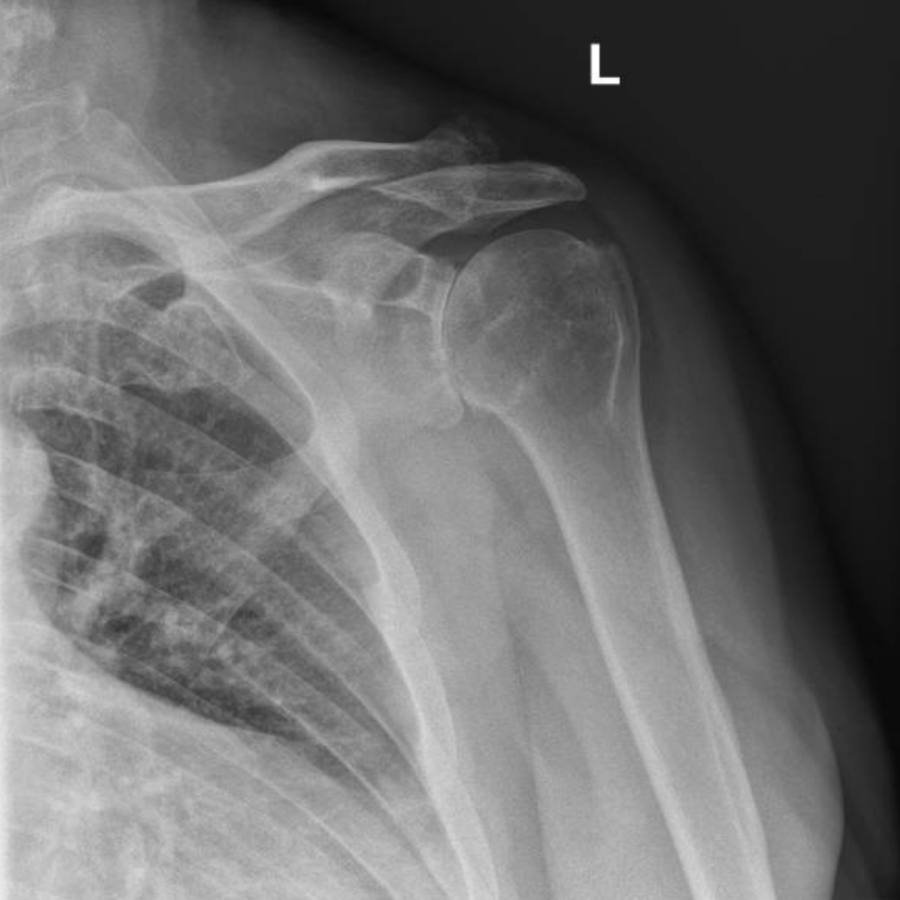

Arthritis of the shoulder is a condition where the smooth protective cartilage coverings on the ends of the bones making up the shoulder joint have worn away. Arthritis of the shoulder is less common than arthritis affecting the hip or knee. However the symptoms can be very disabling and can affect the function of the whole arm as well as causing severe pain.

Surgery is considered when other treatments are no longer effective in controlling your symptoms. Shoulder joint replacement is a very effective treatment for shoulder arthritis. The operation removes the arthritic joint surfaces and replaces them with a combination of metal and plastic surfaces. This operation is extremely successful in controlling pain and improving function of the shoulder and the whole arm. If you are being treated for shoulder arthritis and would like to find out more about shoulder replacements, or if your current treatments are not working, please book an appointment at The Cheshire Shoulder and Elbow Clinic.